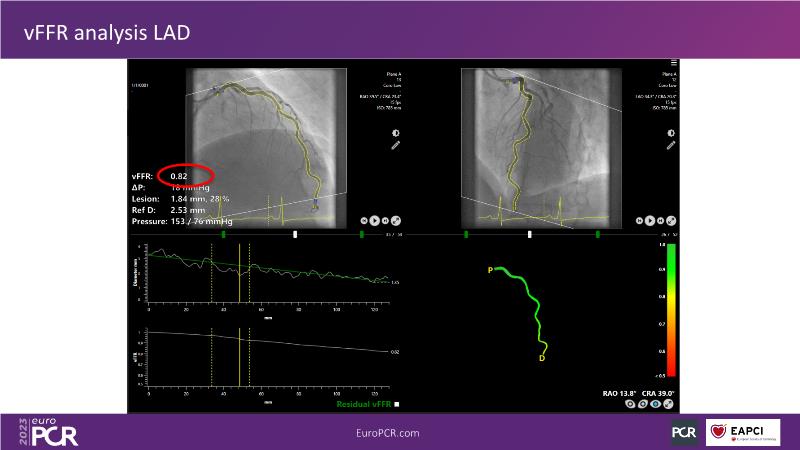

Explore angiography-based FFR/virtual FFR in this session. Uncover clinical evidence, identify ideal patients, and learn step-by-step integration into daily practice.

• To know the clinical evidence behind angiography-based FFR/vFFR

• To learn step by step how to apply it in your daily practice